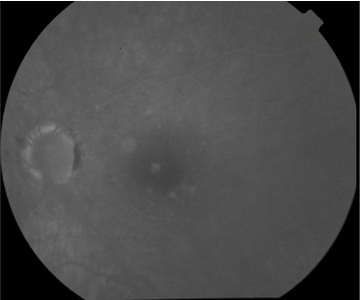

FUNDUS DESCRIPTION: |

OD OS |

OD Red-Free: Pre-Injection: Arterial: A-V: Venous: Recirculation: Late:

OS Red-Free: Venous: Recirc: Late:

Impression